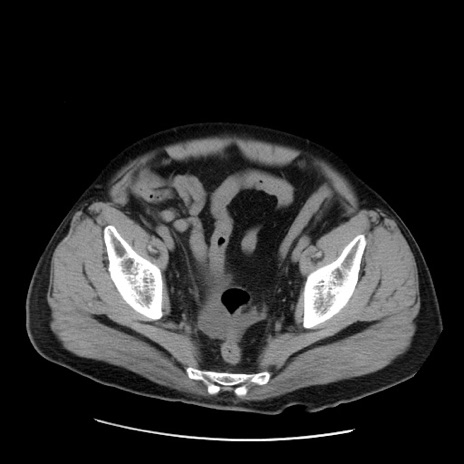

症例20(横断像)

【症例】 60歳代男性

【主訴】 腹部膨満、嘔吐

【現病歴】5日前頃より倦怠感を認め食事量減少し4日前の朝嘔吐、食事摂取困難となった。 3日前近医受診し点滴施行され整腸剤などを処方された。 当日他院を受診し、腹部膨満著明、炎症反応の上昇(CRP10.8、WBC11200)あり、紹介受診となる。

【身体所見】 意識JCS1 受け答えがはっきりしないBP 111/57mHg、 P 67bpm、、BT35.2°C、SpO2 97%(RA)、 腹部:膨隆、打診で鼓音あり、全体的に圧痛有り、腸蠕動音(-)、反跳痛ははっきりせず。

【データ】WBC 11400、CRP 14.20